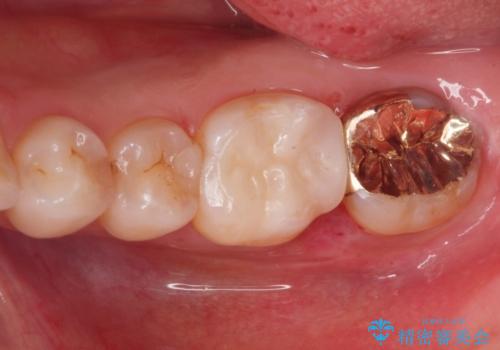

- 歯が黒くて虫歯じゃないかと心配して来院。

過去にプラスチックの樹脂で治療されており、歯とプラスチックの隙間から虫歯が進行していました。

拡大鏡下で虫歯を除去し、詰め物にて治療しました。

一番奥の歯は歯の高さが足りない、噛む面を覆う面が広くなってしまい、セラミックの詰め物だと割れるリスクが高くなってしまうので手前はセラミックインレー奥の歯はゴールドインレーにて治療しました。